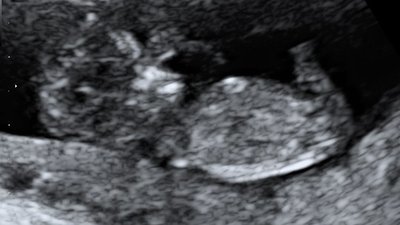

Research shows that fathers are becoming more likely to experience post-natal depression, and that they may experience more challenges bonding with their baby, given they do not feel the same hormones as the birth parent, nor have the intimate opportunity of bonding with the baby in utero. The ultrasounds are a key time for fathers and non-birth parents to begin their relationship with their child, and start to form this bond.